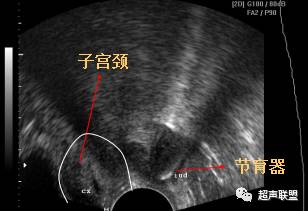

(经阴道超声)

节育器外游

节育环(IUD)位于宫颈(CX)左侧的盆腔内.

超声表现为子宫腔内无节育器显示,节育器可穿透宫壁落入腹腔,包裹于肠管中,从而形成纤维粘连或机化,在腹腔内、阔韧带、附件区或直肠窝区有强回声节育器图像。节育器外游至盆腔,因肠道气体干扰不易寻找,应多角度仔细观察,节育器外游至肠间与肠道气体相混不易分辨,超声仪无能为力,须借助X线检查。偶尔IUD可穿入膀胱,此时可见带有彗星尾征的强回声带穿过膀胱壁而进人膀胱腔。鉴别诊断:节育器外游至膀胱须与膀胱结石相鉴别,结石随患者体位不同而改变,位置变化较大,节育器多因炎性粘连而固定不动。